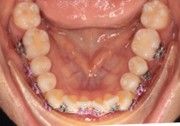

The right side shows a full C-bend from cinching too far from the bracket, then re-bending with a regular Hammerhead plier from a different brand.

The right side shows the distortion produced while bending with a regular Hammerhead plier from a different brand.

The right side has an acute (distorted) bend after bending the wire with a regular Hammerhead plier from a different brand.